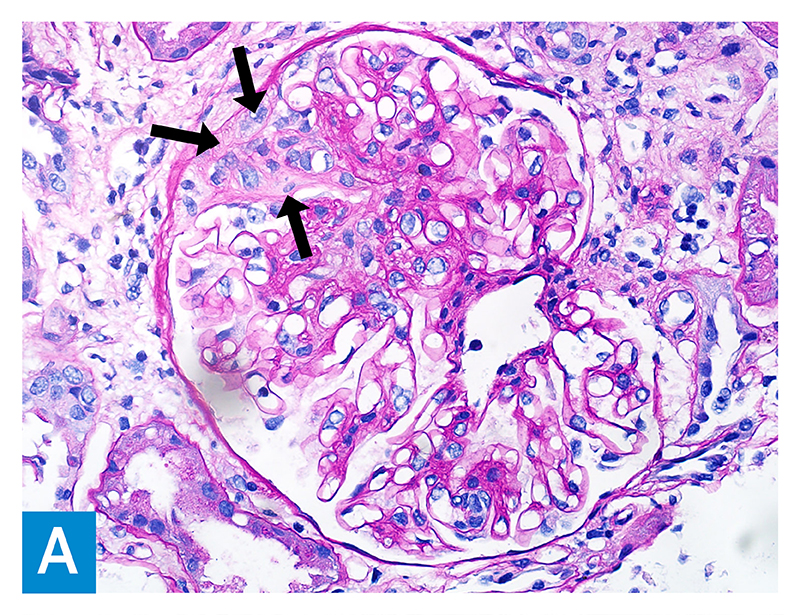

Four months prior to admission the patient’s serum creatinine was 2.0 mg/dL compared to a recent baseline of 0.9 mg/dL. A high titer proteinase 3 (PR3) antibody (294 immunoassay) was detected, and renal biopsy demonstrated active and chronic crescentic glomerulonephritis superimposed on immune complex glomerulonephritis (Figure 1). Laboratory studies were notable for positive serum cryoglobulins, rheumatoid factor greater than 450 IU/mL, and polyclonal hypergammaglobulinemia. Pertinent negative values included antinuclear antibody, anti-glomerular basement membrane antibody, viral hepatitis studies, and blood cultures. He had received outpatient methylprednisolone 1000 mg IV daily for 3 doses.

Figure 1A: PAS staining of the glomerulus (400× magnification) showing a fibrocellular crescent in the Bowman space with capsular adhesion (arrows), adjacent to the glomerular capillary tuft, which appears normal in other areas.